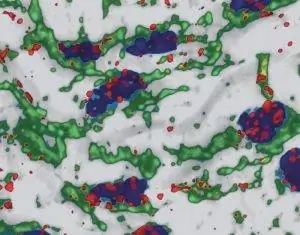

Однако, как теперь обнаружили исследователи, микроРНК в клетках кровеносных сосудов могут иметь и другие эффекты. Триггером является сильное сдвиговое напряжение, которому подвергаются эндотелиальные клетки внутренних стенок сосудов в местах с сильной турбулентностью кровотока - например, в местах впадения мелких вен. На эти условия реагирует специфическая микроРНК, которой очень много в эндотелиальных клетках.

МикроРНК miR-126-5p соединяется с пузыревидной транспортной молекулой в клеточной плазме, когда ее домашняя клетка подвергается сильному сдвиговому напряжению, как сообщают Сантовито и его коллеги. Затем этот везикул переносит фрагмент РНК в ядро клетки. Там микроРНК отсоединяется от своего переносчика и вместо этого связывается с ферментом каспазой-3, как показали эксперименты на клеточных культурах. Это присоединение микроРНК блокирует функцию каспазы-3.

Но, ингибируя каспазу-3, микроРНК защищает эндотелиальные клетки от гибели - по крайней мере, в нормальных условиях. Таким образом, miR-126-5p предотвращает повреждение, которое способствует возникновению артериосклероза в областях стенки сосуда, подверженных сильному стрессу. Эта ранее неизвестная функция этого фрагмента РНК вносит решающий вклад в защиту кровеносных сосудов и предотвращение кальцификации сосудов.